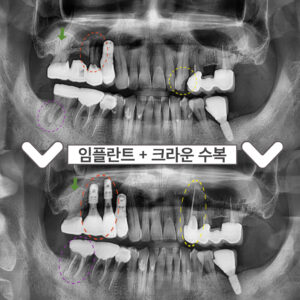

부천서울이로운치과 과거에 치료받았던 보철이 불편하다면? 안녕하세요! 부천서울이로운치과 대표원장 이경중입니다 🙂 앞니는 어금니와 달리 우리가 말할 때나 음식을 먹거나 미소를 지을 때 외부로 드러나 보이는 부분이기 때문에 심미적인 부분에서도 중요한 부분을 차지하게 되는데요. 그렇게 때문에 적절하지 못한 보철물로 인해 보기 좋지 않거나, 잇몸 건강에 문제가 있는 경우 재보철을 통해 더보기…